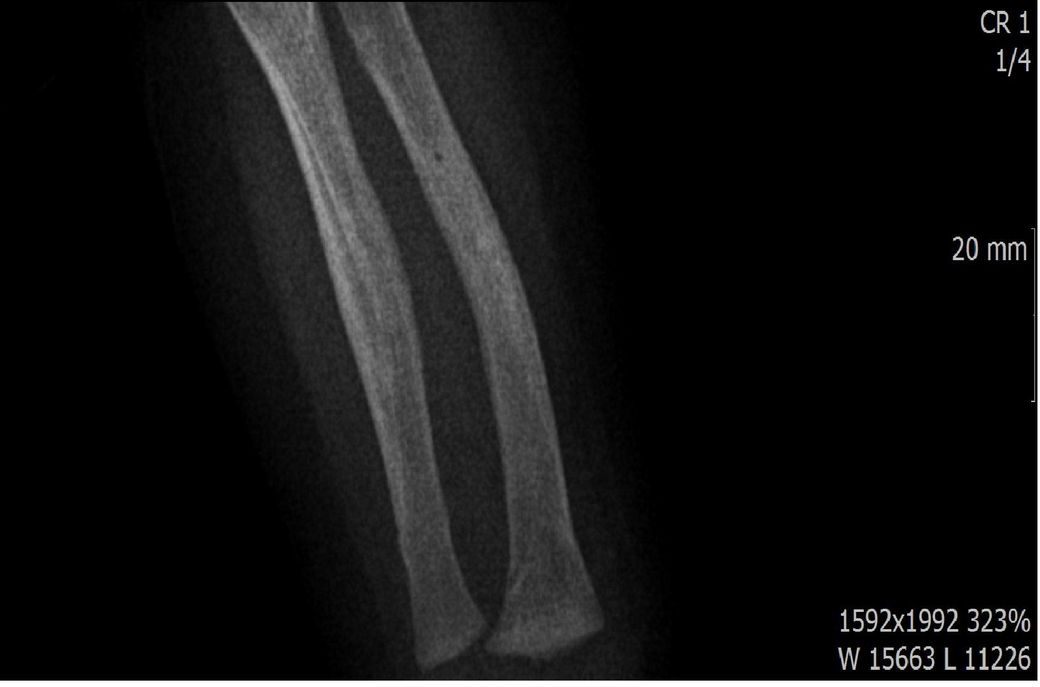

다름이 아니라, 첨부드린 엑스레이(X-ray) 사진처럼 골절 사실을 알게 되고 골절 발생 시점 대략적으로나마 추정시기를 파악하려고 문의 드리게 되었습니다

1) 3월 30일 촬영한 X-ray만으로 정확한 골절 시기를 100% 특정하는 데에는 한계가 있다는 점 충분히 인지하고 있기에 촬영날짜 기준으로 대략적으로 어느정도 시점에서 발생되었을 것으로 추측(ex 당일, 7~10일전, 7~14일 전, 10일 ~ 20일전, 14일 ~ 30일전 등등등)되는지 이해하고 싶습니다.

첨부드린 파일에는 없지만 4월 5일 사진에서는 캘로스 라는 것이 발견된다고 합니다.

• 3번 째 사진